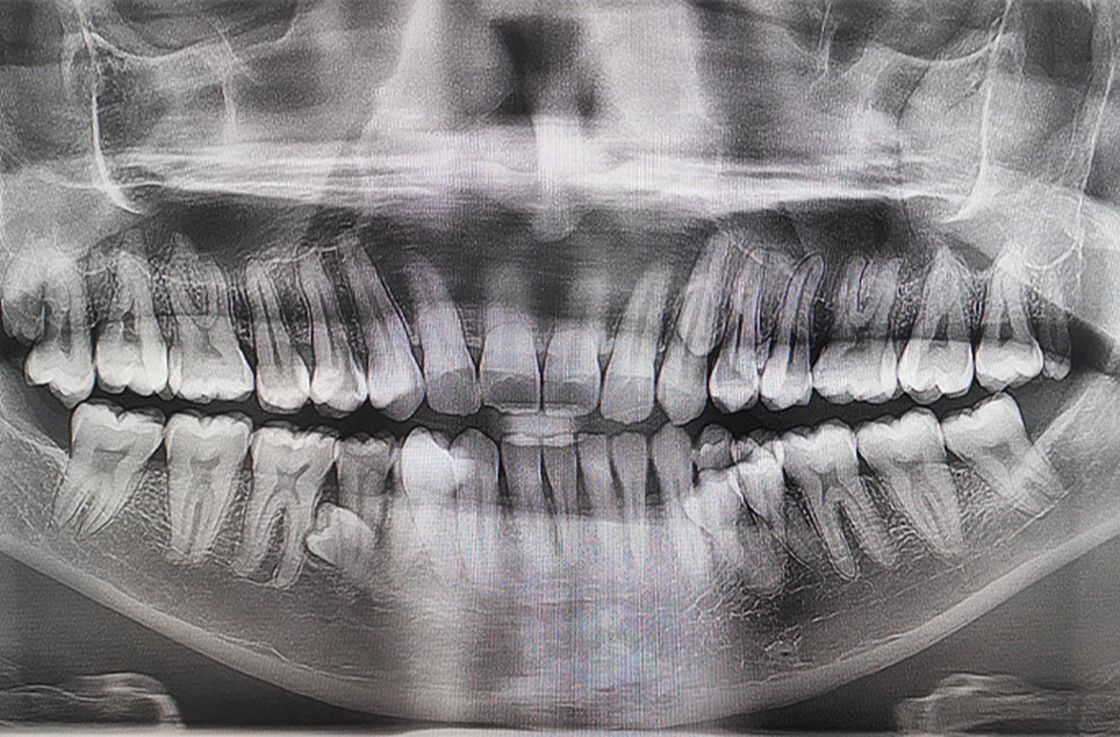

Малайзияда тұратын бір баланың әкесі Пратаб Мунианди аузындағы тіс санының көптігінен әлем бойынша рекорд орнатқан. Муниандидің өзге адамдармен салыстырғанда 10 артық тісі бар, деп хабарлайды guinnessworldrecords.com сайтына сілтеме жасаған KAZ.NUR.KZ.

42 тісі бар азаматты 2023 жылы екі стоматолог тексеріп, сол жылы ол әлемдік рекорд орнатады.

"Тісімнің көптігін алғаш рет 2021 жылы отбасылық шай ішу кезінде байқап, отбасыма артық тістер өсіп жатқанын айттым. Біз тістерімді бірге санап шықтық, ол кезде менде 38 тіс болды. Кейінірек тіс рентгені әлі шығып үлгермеген тағы төрт тісім бар екенін көрсетті. 2023 жылдың басында менде барлығы 42 тіс бар екенін түсіндім. Бақытыма орай, тісім түзу және ешқандай асқынулар жоқ", - дейді ол.

Ал Калпана Балан (Үндістан) — аузындағы тістердің саны бойынша рекорд орнатқан әйел, оның барлығы 38 тісі бар.